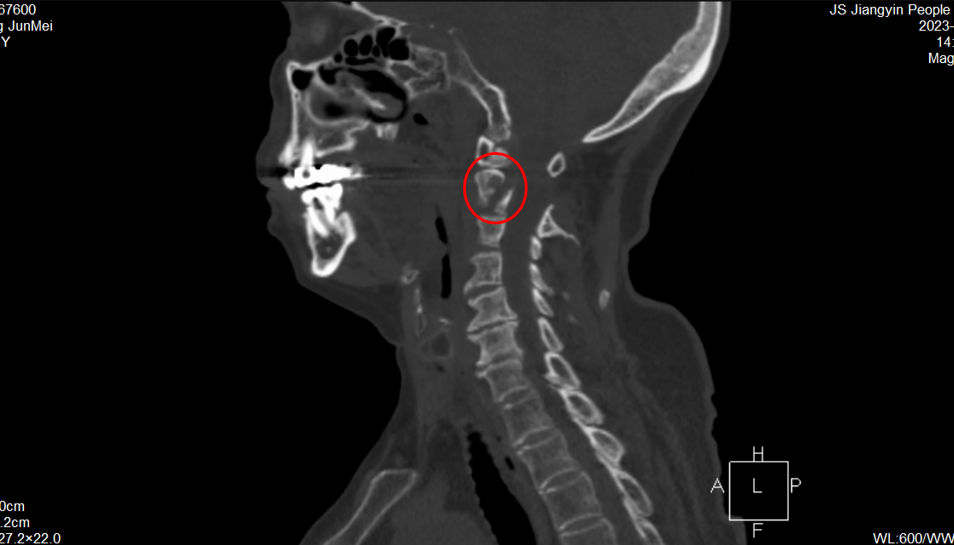

今年81歲的張奶奶因頸部外傷導(dǎo)致頸部疼痛伴活動(dòng)受限入院就診。核磁共振檢查顯示,老人樞椎椎弓根骨折伴局部骨髓挫傷水腫,如若不及時(shí)手術(shù),很快就會(huì)癱瘓、繼而影響呼吸功能,甚至危及生命。

張奶奶術(shù)前CT